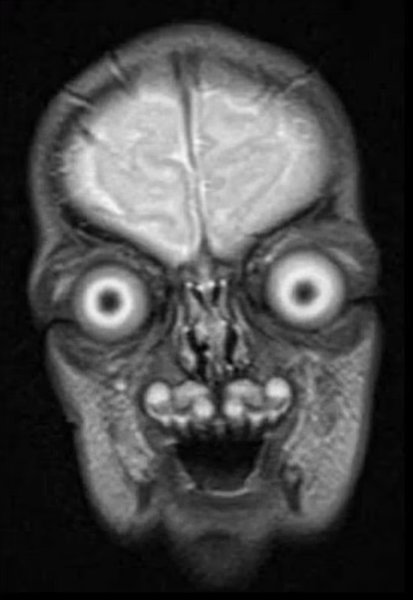

З витріщеними очима та диявольською посмішкою: деталізовані МРТ-скани плода до смерті налякали мережу

Жахливі знімки можуть здатися кадрами фантастичного фільму про прибульців або демонів, але дослідники запевняють, що вони реальні.

Дивлячись на кадри, легко подумати, що вони взяті з якогось голлівудського науково-фантастичного фільму про прибульців, а можливо навіть фільму жахів. Однак дослідники непохитні: на жаль, скани справжні — саме так виглядає людське немовля в утробі матері, якщо дивитися на нього через МРТ.

Однак МРТ пропонує жахливо деталізовані чорно-білі зображення, які часом ставлять батьків у глухий кут. Якщо ви думали, що на скані МРТ малюк буде дуже чарівним, на жаль, це зовсім не відповідає дійсності.

На думку одного з користувачів соціальних мереж, МРТ не рекомендується робити під час вагітності, щоб батьки не злякалися та не зрозуміли, що "виношують демонів кошмарів". Інші порівнюють чорно-білі знімки немовлят з кадрами фільмів Тіма Бертона про прибульців, а треті взагалі називають малюків не інакше як "вилупком диявола".

Втім, поки одні травмовані переглядами таких зображень, інші, схоже, знаходять їх дуже кумедними. Користувачі також припустили, що знімки насправді можуть бути фейками, проте дослідники провели перевірку та підтвердили їхню справжність: мінімум два з них були опубліковані Гарвардською медичною школою.

Вчені розповіли, що МРТ використовує магнітні поля та радіохвилі для отримання докладних зображень внутрішньої частини тіла. Наші очі та мозок мають вищий рівень "сигналу" (радіохвиль), а тому виглядають яскравішими й виділяються на зображеннях. Інші частини тіла випромінюють нижчі рівні, а тому здаються темнішими.